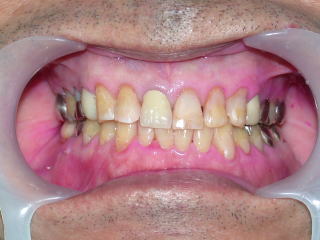

右下7番の欠損部分にインプラントを植立しました。

一番奥の白い歯です。